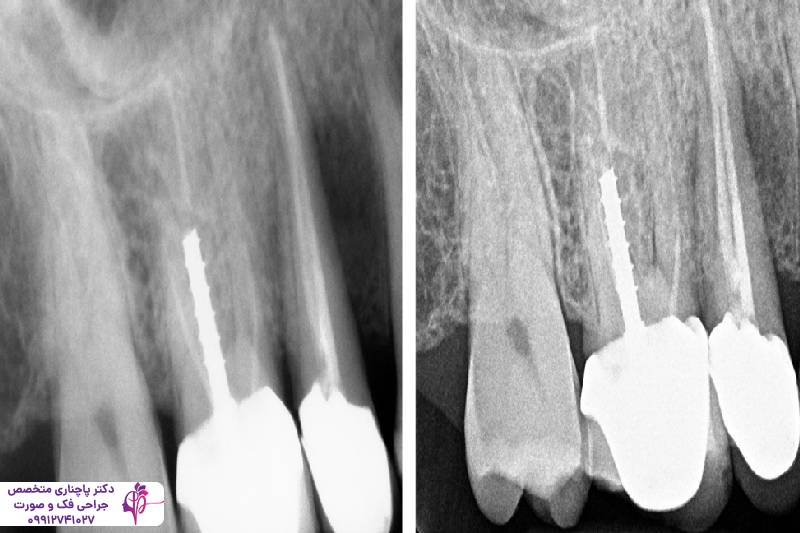

ایمپلنت دندان یکی از موثرترین روشها برای درمان تحلیل استخوان فک و جلوگیری از پیشروی آن است. پایههای تیتانیومی ایمپلنت مثل ریشه دندان طبیعی عمل میکند و با تحریک بافت استخوان جلوی تحلیل رفتن آن را میگیرد. گرچه کاشت ایمپلنت به یک بستر قوی و مناسب نیاز دارد و در صورتی که استخوان فک تراکم خود را از دست داده باشد باید با درمانهای جانبی مثل پیوند استخوان بستر مناسب برای کاشت ایمپلنت را آماده کرد.

پیوند استخوان

پیوند استخوان یکی از کلیدیترین روشها برای درمان تحلیل شدید استخوان فک است. در این فرآیند بافت استخوانی جدید را به ناحیه آسیبدیده اضافه میکنند. این بافت استخوانی جدید هم میتواند از بدن خود بیمار باشد که معمولا با پیوند استخوان فک لگن انجام میشود، یا باید از منابع صنوعی یا حیوانی باشد. این بافت جدید به تدریج با استخوان طبیعی فرد ادغام میشود و حجم و تراکم استخوان به حالت طبیعی برمیگردد. معمولا بعد از پیوند استخوان فک ایمپلنت انجام میشود ولی دوره نقاهت پیوند استخوان باید کامل شود و بعد ایمپلنت انجام دهند.